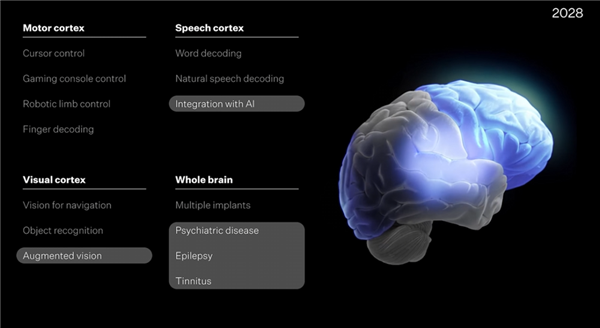

迈向混合智能系统的关键一步——“人脑芯片”一周学会复杂电脑游戏